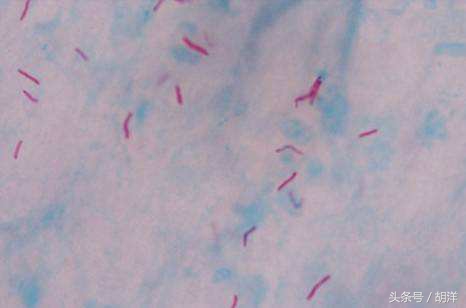

得了肺结核,为了明确诊断,必须要查到结核菌,那么检查结核菌的方法有以下几种。

第一是痰液检查

痰液是结核传染的重要途径同时,也是临床上查找结核菌的重要方法,因为它便宜,而且没有什么痛苦,所以,对于病人来说这是最好,也是最适合的检查方法。